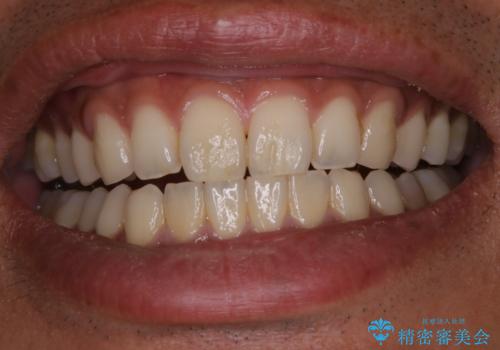

PMTCで清潔感のある明るい口元に

- 歯の色が気になるため、どの処置が適しているか相談してから施術をして欲しいとのことで来院されました。

全体的に汚れが付着していたため、まずはPMTCでご自身の本来の歯の状態にしてから、ホワイトニングにいついて考えましょうとなりました。

PMTCを行うことで、ご自身本来の歯の色になり自然な明るさになります。